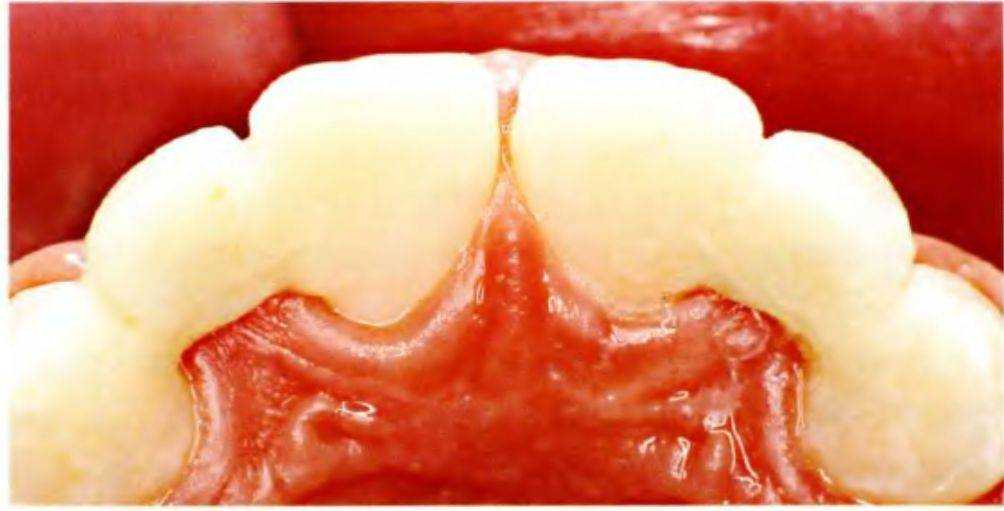

Рис. 5-Зе. Увеличенные пространства (небный вид)